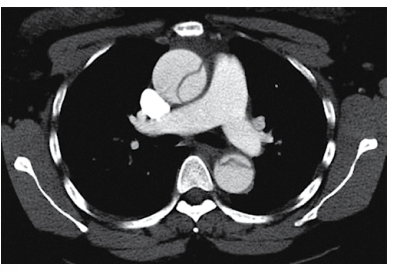

Homem de 49 anos é atendido no pronto-socorro com o relato de dor súbita e intensa no tórax anterior há cerca de 1 hora. O histórico é notável para tabagismo e hipertensão arterial, em uso de enalapril e clortalidona. Nega uso de drogas ou álcool. Ao exame físico: ele encontra-se pálido, sudorético, ansioso, agitado, referindo dor intensa no tórax anterior e posterior; pressão arterial: 194 x 115 mmHg; pulso: 1155 bpm; oximetria de pulso: normal. Glicemia capilar: 125 mg/dL. ECG sem indícios de isquemia. Analgesia intravenosa é prescrita e a angiotomografia de tórax realizada é mostrada a seguir.